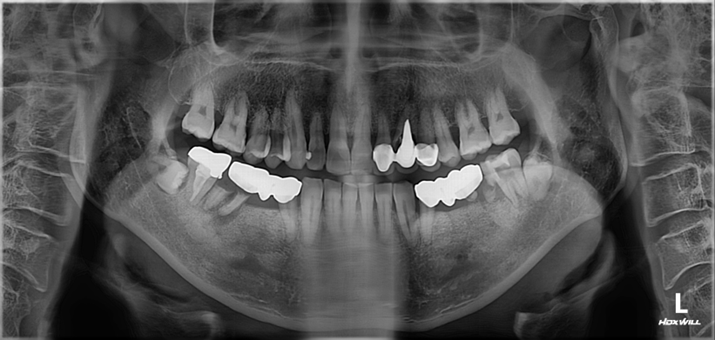

양쪽 어금니 임플란트 치료 #2

작성자

최고관리자

조회

689

작성일

23-07-13